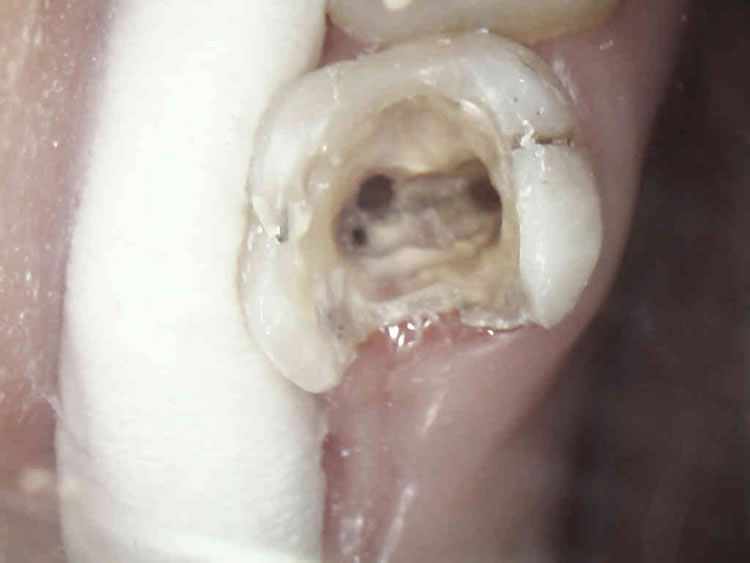

Slijedeći korak je prikazivanje endodontskog prostora tj. "otvaranje zuba" tijekom kojeg doktor dentalne medicine uklanja ostatke upaljenog ili nekrotičnog tkiva i pronalazi korijenske kanale. Ukoliko je pulpa vitalna, tj. živa, područje se prethodno anestezira jer je zahvat u protivnom jako bolan. Potom slijedi instrumentacija korijenskih kanala pri čemu doktor dentalne medicine tankim iglicama ulazi u kanale. Njima se uklanjaju ostatci tkiva i detritusa, čiste i šire korijenski kanali po pravilima struke.

Kanal se širi iz razloga da se olakša uklanjanje nepoželjnog sadržaja te da se isti može hermetički napuniti. Kad je kanal pripremljen, puni se gumastim materijalom ( štapićima ) i cementom.